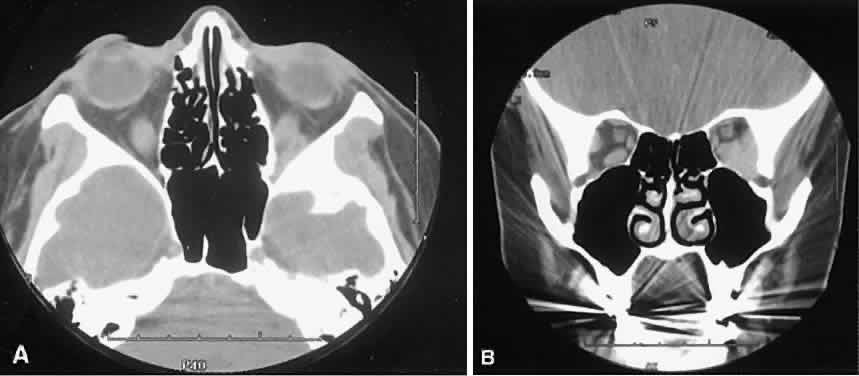

Optimal visualization of the orbit requires imaging from at least two planes. Axial slices should be oriented parallel to the optic nerve (-10 degreesto the orbitomeatal line) and no thicker than 3 mm. Axial views, because of volume averaging, may miss lesions located along the floor or roof. Additional views, typically coronal, can be obtained by reformatting data obtained during axial imaging or by direct coronal scanning.

Direct coronal views usually are preferable because of better resolution.6,7 They can be obtained by having patients lie either prone or supine, extending their neck, and angulating the gantry sufficiently to provide coronal imaging while avoiding artifacts from the teeth. Direct coronal scans also should be no thicker than 3 mm.

Coronal views may need to be reformatted from axial scans if a patient has extensive dental fillings, is anesthetized, or cannot extend the neck sufficiently for direct coronal scanning. The resolution on these images can be improved if data are collected from 1.5-mm contiguous axial slides.6 Spiral CT has resulted in improved multiplanar reformation with thin section (1 to 1.5 mm) axial images. High-resolution images necessary for leukocoria or foreign body imaging are obtained with 1-mm axial slices at 1:1 pitch at 1-mm intervals. Ideally, most screening orbit studies are performed at 3-mm direct axial and direct coronal images.

An appreciation for the various pathologic processes that affect the orbit is facilitated by an understanding of the normal orbital anatomy (Fig. 1). The orbit is a pyramid-shaped bony structure bounded inferiorly by the maxillary sinus, medially by the ethmoidal sinus, and superiorly by the frontal sinus. The sphenoidal sinus is situated posteriorly along the medial orbital wall and has a common wall with the optic canal. The lacrimal gland lies within its fossa located in the superior temporal aspect of the orbit and can be seen on both axial and coronal views.

The extraocular muscles (EOMs), with the exception of the inferior oblique, originate from the anulus of Zinn in the orbital apex. The inferior oblique takes its origin from the frontal process of the maxilla and is seen occasionally on CT imaging. The superior oblique, after originating from the anulus, courses along the superior nasal orbital wall just above the medial rectus muscle before passing through the trochlea. The rectus muscles conveniently form a muscle cone, which is sometimes helpful in terms of differential diagnosis. Before thinner axial slices and multiplanar imaging were available, an enlarged inferior rectus muscle often was imaged as an apical mass, especially if dysthy-roid optic neuropathy was present. The importance of imaging from two different planes cannot be overemphasized in this situation.